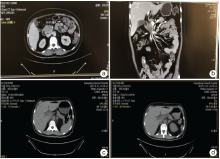

徐× × , 女性, 53 岁。因“ 发现血象异常1个月” 于2017-07-07 第一次入院。查体:T36.8℃, P86 次/分, R20 次/分, Bp144/80 mmHg, 体质量70 kg, PS 评分1 分。贫血貌, 余未见阳性体征。既往有糖尿病、高血压病史。无化学性、放射性物质接触史; 无肿瘤家族史。2017-07-07 全血常规:白细胞计数0.75× 109/L↓ 、血红蛋白浓度74 g/L↓ 、血小板计数140× 109/L、中性粒细胞计数0.21× 109/L↓ 。完善骨髓检查确诊为急性髓系白血病(acute myelocytic leukemia, AML)中危。2017-07-11 胸腹部增强CT提示:胰头部软组织肿块(30 mm× 29 mm)累及十二指肠壁和肠系膜上静脉, 考虑可能胰头癌, 见图1a和图1b。2017-07-19 B超提示左侧乳腺12点钟位置实质性病灶伴钙化(1.6 cm× 0.9 cm), 形态不规则, 边界不清, 呈“ 蟹足样” 改变, 后方回声衰减, 内部回声不均匀, 可见散在分布强回声光团, 可能乳腺癌, 见图2。 CA199为38.52 U/ml↑ 。肝肾功能、风湿免疫指标、凝血指标、尿常规、粪便常规、CA-125、CA15-3、CA72-4、肿瘤二项、甲状腺功能三项、感染指标未见明显异常。请普外科、介入科会诊, 考虑为胰头肿瘤, 但患者病变部位血管丰富, 组织疏松, 且急性白血病诊断明确未缓解, 穿刺风险高。与患者家属详细解释病情以及治疗风险等, 患者及家属不同意行PET/CT检查, 不同意穿刺等进一步明确胰腺、乳腺病灶的性质, 同意化疗治疗白血病。2017-07-22 予NA 方案(米托蒽醌针+阿糖胞苷针)化疗, 复查骨髓原始细胞仍然高(原始细胞94%), 白血病未缓解。2017-09-13 复查 CT提示胰头部病灶较前似稍缩小(30 mm× 20 mm), 见图1c, 考虑沟槽区胰腺炎与胰头癌, 建议相关检查鉴别。2017-09-16予以NAE方案(米托蒽醌针+阿糖胞苷针+依托泊苷针)化疗, 复查骨髓提示为部分缓解(原始细胞16%), 血象较前恢复。

2017-11-09患者因“ 急性髓系白血病伴胰腺、乳腺肿物4个月” 再次入院。患者一般情况可, 无发热、黄疸、腹痛等不适。查体:T36.4 ℃, P67 次/分, R20次/分, Bp142/72 mmHg, 体质量65 kg, PS评分1分。贫血貌, 全身皮肤黏膜未见黄染, 浅表淋巴结未触及肿大, 胸骨无压痛。心肺未见异常。腹软, 全腹无压痛, 肝脏增大, 剑突下约9 cm, 右锁骨中线下约5.5 cm, 表面光滑, 质软, 边缘光整, 脾脏肋下未触及。入院主要诊断:①急性髓系白血病(中危, 难治, 部分缓解), ②胰腺肿物(白血病髓外浸润?胰头癌?), ③乳腺肿物(白血病髓外浸润?乳腺癌?)。2017-11-14 复查CT(见图1d):胰头部病灶 29 mm× 20 mm, 较前(2017-09-13 CT图1c)相仿, 胆道系统受压扩张较前稍加重。2017-11-14 复查 B超提示左侧乳腺12点钟至1点钟位置实质性病灶(1.6 cm× 1.0 cm)伴粗大钙化, 建议进一步检查。2017-11-17 行左乳腺病灶穿刺, 病理未见明确恶性证据, 病理诊断为乳腺腺病。

入院1 周后, 患者出现黄疸, 监测CA-125、CA199、胆红素进行性增高。2017-11-21, CA-125为36.9 U/ml↑ , CA199为626.4 U/ml↑ ; 2017-11-23 TBIL为217.2 μ mol/L, DBIL为119 μ mol/L, 考虑胰头肿物合并梗阻性黄疸。请相关科室会诊, 建议行内镜下经十二指肠乳头支架置入或经皮经肝穿刺胆管引流, 与患者及家属沟通病情后, 2017-11-27转普外科行内镜下经十二指肠乳头支架置入术; 造影见胆总管下段狭窄约4 cm, 胰管开口狭窄, 主胰管可见节段性狭窄、扩张; 胆总管下段置8F金属支架, 胆汁引流通畅, 术程顺利; 术后黄疸减轻, 监测胆红素进行性下降, CA-125、CA199 仍持续增高, 2017-11-30 CA-125为45.1 U/ml↑ , CA199为1 000.1 U/ml↑ 。2017-12-05 PET/CT(图3)示:胆总管-胰头-胃窦部-十二指肠球降部肿胀, 肝S3 结节, 胸骨柄骨质破坏, 葡萄糖代谢不同程度增高; 考虑恶性肿瘤病变, 血液系统恶性肿瘤以上部位浸润与胰腺癌伴转移鉴别, 建议组织学检查。左侧锁骨上、腹膜后及肝门部多发增大淋巴结, 部分糖代谢稍增高; 考虑良性增生性淋巴结可能性大, 不除外部分为早期转移淋巴结, 建议随访。左侧乳腺考虑良性病变。